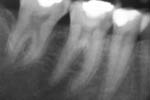

Revisionsbehandlung eines Unterkiefermolaren (37) vor geplanter Überkronung (Dr. Maik Göbbels) Download